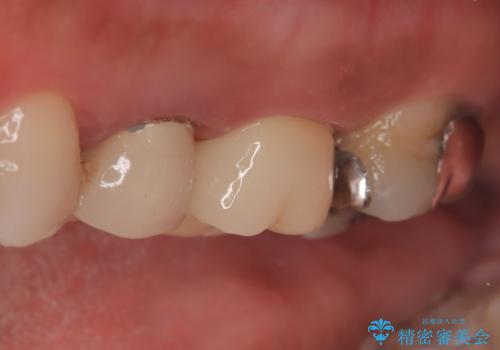

【破折ファイル除去】他院で折れた根管治療の器具をとってほしい

- 他院で折れた根管治療の器具をとってほしいという主訴で来院されました。

マイクロスコープで根管内を観察すると、除去できる状態だったため破折ファイル除去を行いオールセラミッククラウンにて修復治療しております。

- 35万円費用は治療当時の料金となります